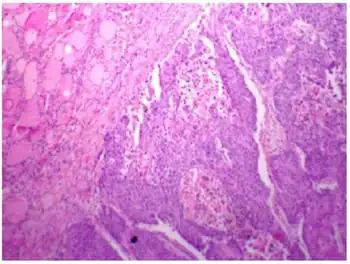

| Micrograph of squamous-cell carcinoma (H&E stain) | |

Squamous epithelial cells are not found in normal thyroid, thus the origin of SCTC is not clear. However, it might be a derived from the embryonic remnants such as thyroglossal duct or branchial clefts. Often SCTC is diagnosed in one of the thyroid lobes, but not in the pyramidal lobe. Another possible way of SCTC development can be through the squamous metaplasia of cells. However, that theory is also controversial, since the Hashimoto's thyroiditis and chronic lymphocytic thyroiditis (neoplasms to be showed squamous metaplasia) are not associated with SCTC. Primary STCT is usually diagnosed in both lobes of thyroid gland. The histopathology of STCT shows a squamous differentiation of tumor cells.